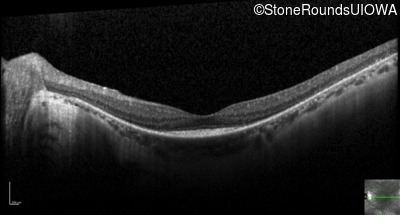

Optical Coherence Tomography - Right - 20/30 +2

Exemplar / OCT Stack